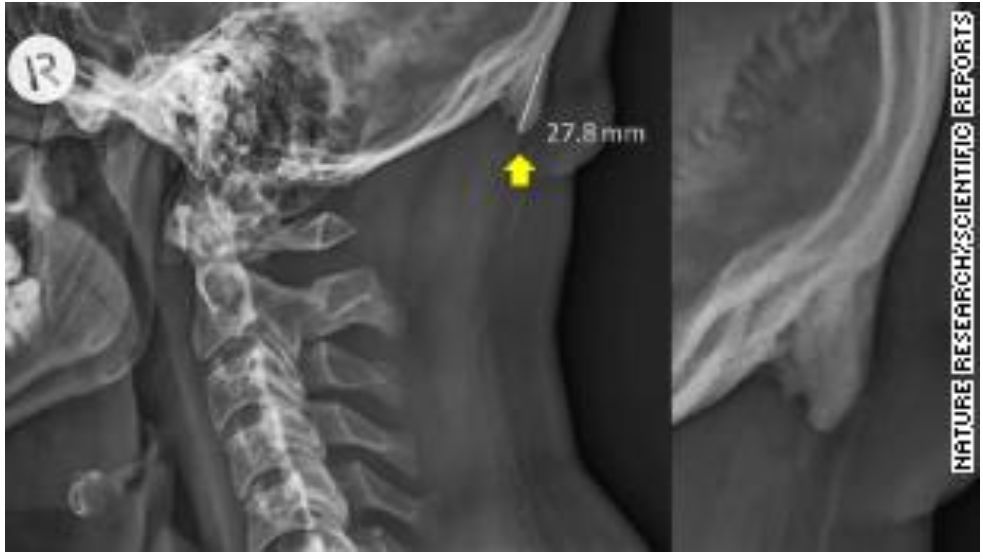

研究中一名28岁男性参与者的X光片,后脑勺长出异常的“角”,还有的人形容成“鸟的喙”“钩子”

这个所谓的“犄角”是什么?其实是指后脑勺下部长出的异常“骨刺”。研究者之一的David Shahar说:“我当医生20年了,最近10年内,我发现越来越多患者的头骨长出了异常的'骨刺'。”

一般在大多数情况下,骨刺的尺寸仅为几毫米,但研究发现年轻人后脑的骨刺长度惊人,最长的有35.7毫米!